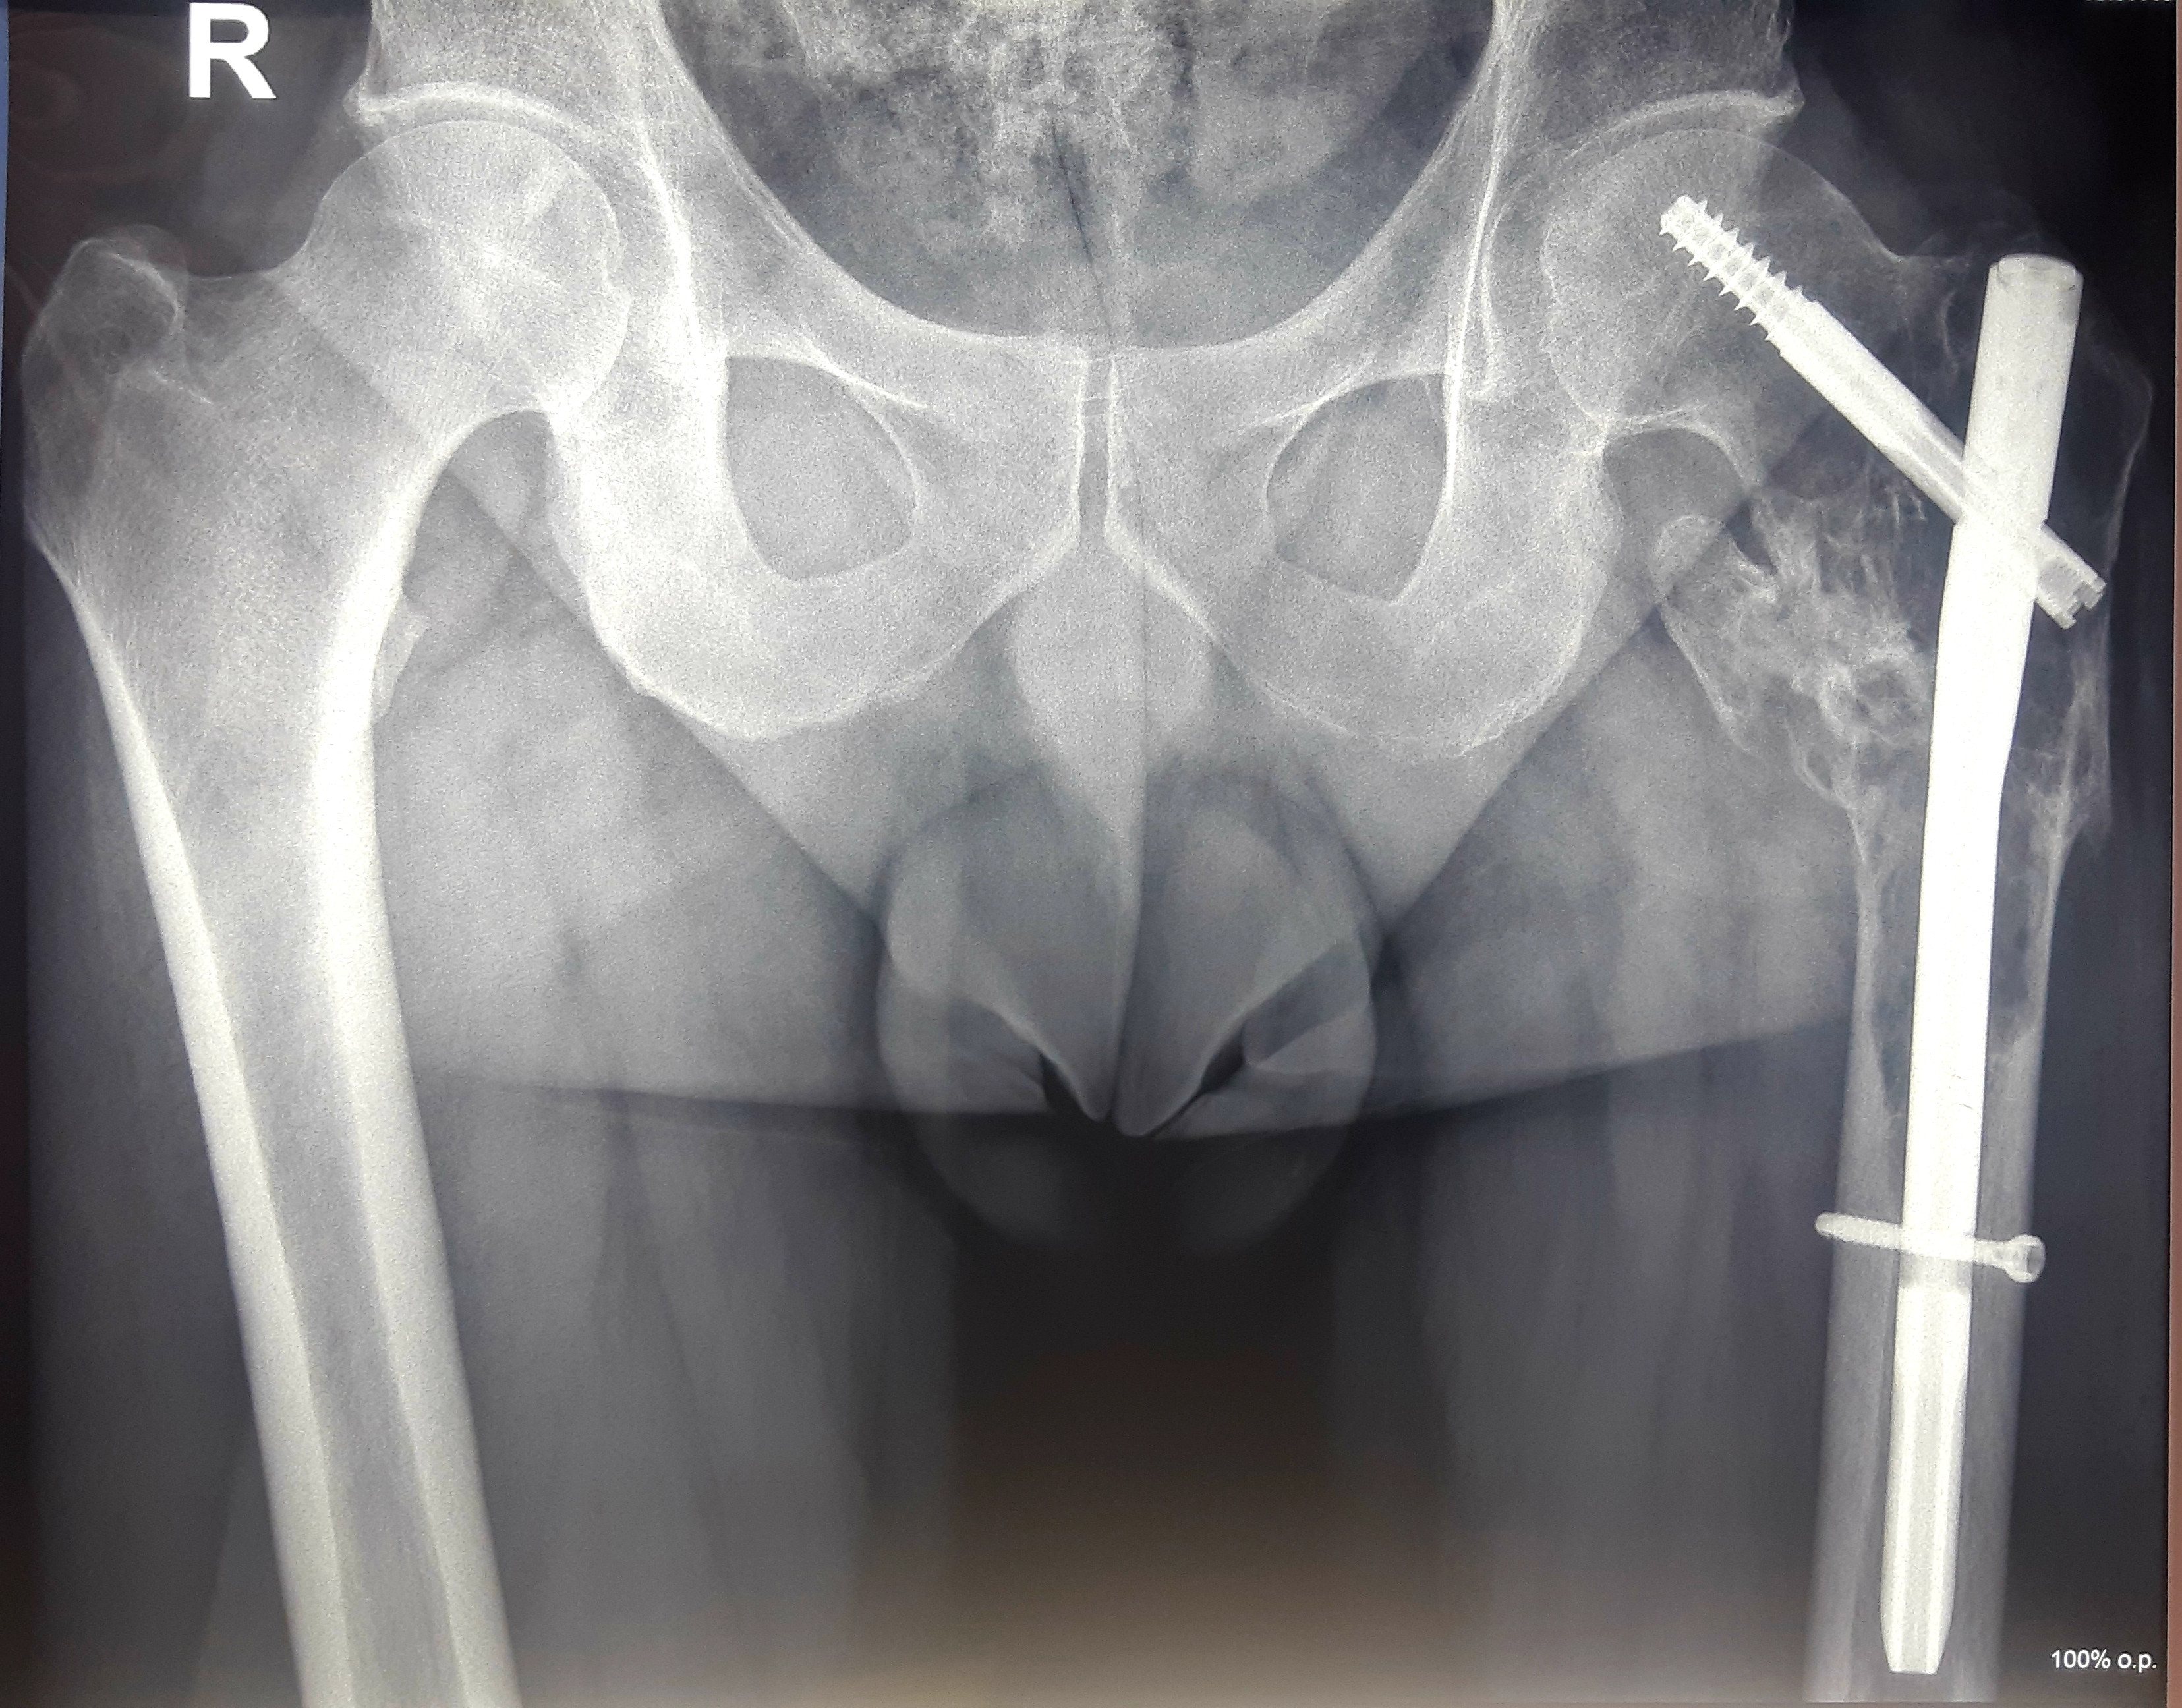

1 . ՌԴ-ում երկրորդային բնույթի կոտրվածքի ֆիքսացիա իրականացնելուց հետո՝ 40-ամյա բուժառուն դիմել է «Նաիրի» ԲԿ։ Բուժառուի մոտ ախտորոշվել է ոսկրային պլազմոցիտոմա։ Քիմոթերապիա ստանալուց հետո՝ 40-ամյա բուժառուն վիրահատվել է։ Կոնք-ազդրային հոդի հետ միասին հեռացվել է ազդրոսկրի վերին երրորդականը։ Առաջացած դեֆորմացիան շտկվել է էնդոպրոթեզով: «Նաիրի» ԲԿ-ի փորձառու թիմի և պրոֆեսիոնալ մոտեցման շնորհիվ՝ հաջողվել է պահպանել բուժառուի գործող վերջույթը։

Վիրահատությունից առաջ

Վիրահատությունից հետո